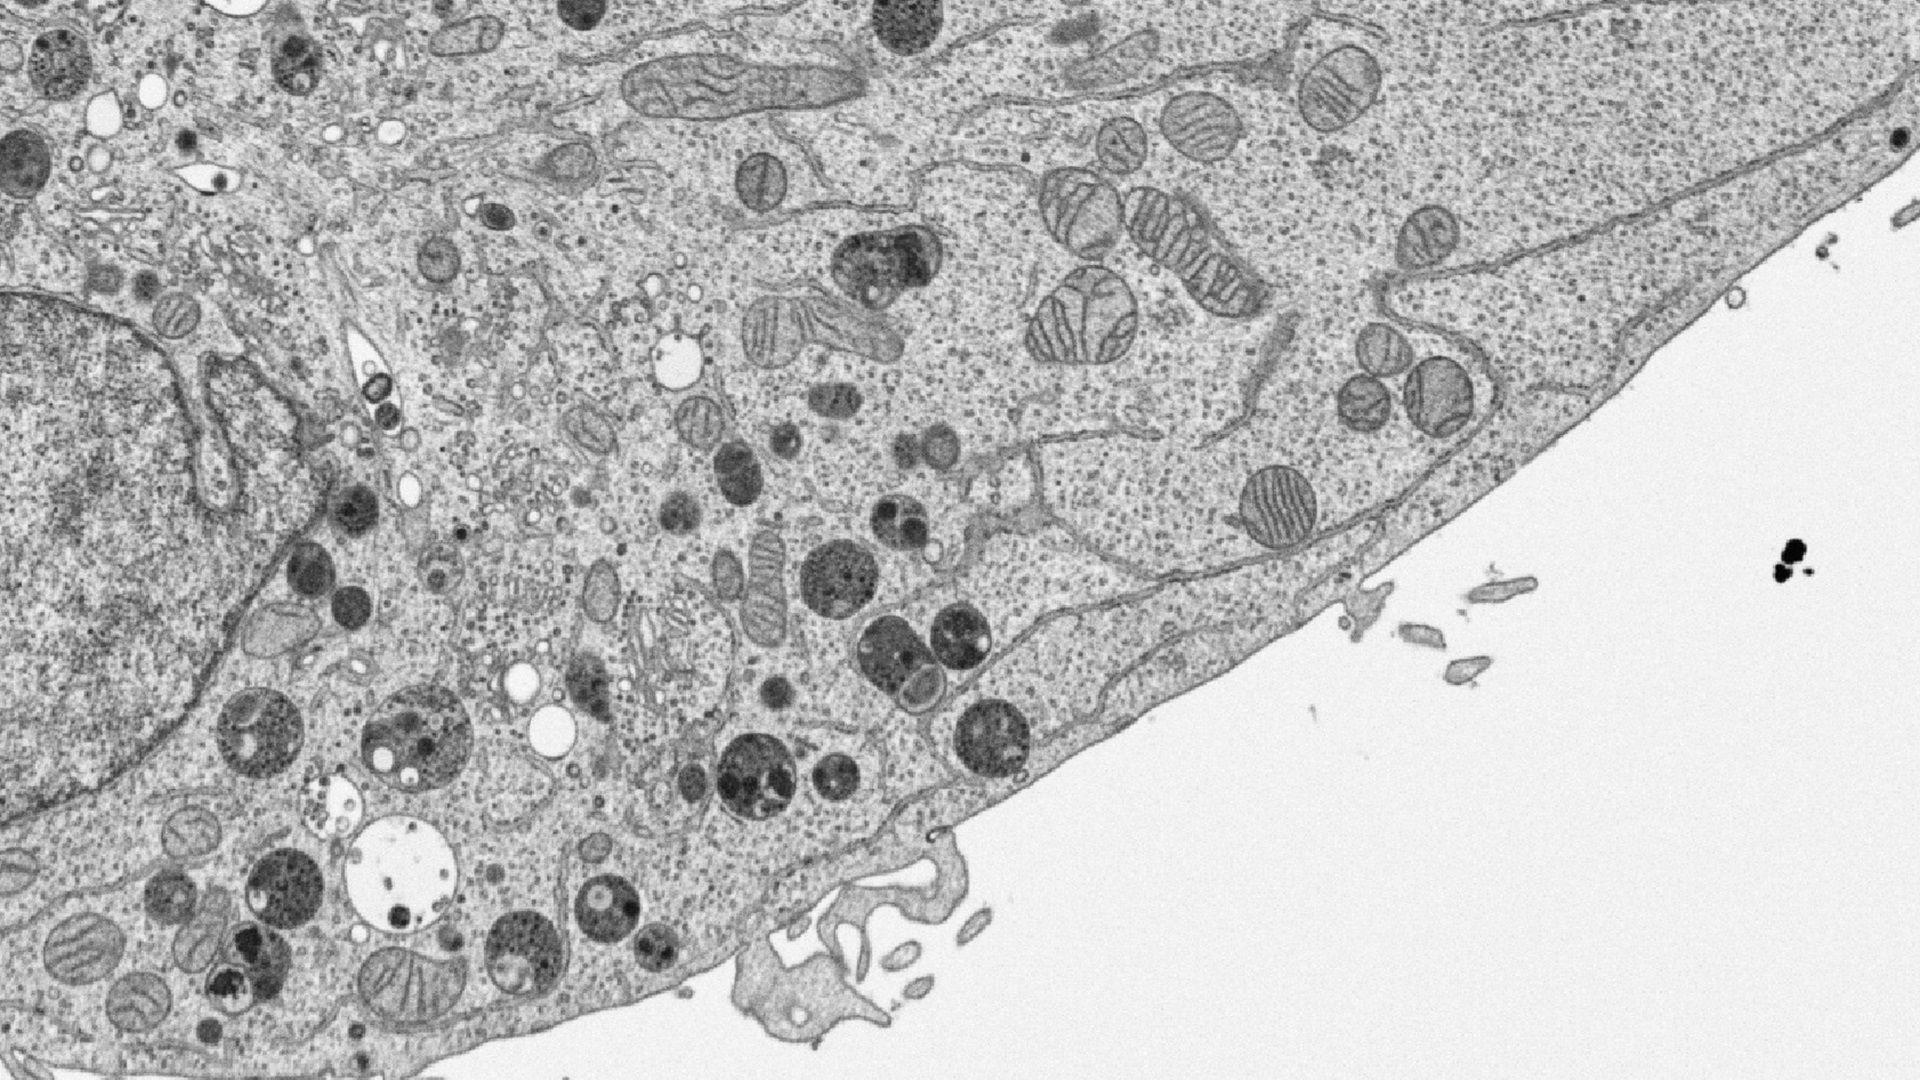

Researchers at Barrow Neurological Institute, Phoenix Children’s Hospital are using transmission electron microscopy imaging and ZEISS arivis Pro (formerly Vision4D) to gain an understanding of how the mitochondria in the brain tissue are affected by hypoxic conditions.

Automated segmentation of the transmission electron microscopy images remains a challenge. ZEISS arivis Pro is specifically designed to allow customers to easily apply the Deep Learning models on the images and run the subsequent analysis within the established workflow tailored to the specific analysis needs. This article describes the best practices in mitochondria EM image analysis: creating the ground truth annotations, running the inference (predictions) in ZEISS arivis Pro, and utilizing its generous toolset for downstream analysis.

The Deep Learning model then was applied to the whole dataset in ZEISS arivis Pro for automated segmentation. We can apply the DL model in the software on the data with the same resolution in the pipeline and scale the resulting objects back to the original size. The pipeline for segmenting the mitochondria was run at 50% scale compared to the original images. Object filtering and classification by the phenotype and export of the numerical data into the Excel format is done automatically within the same pipeline. This enables applying the entire workflow in a Batch mode on a set of images.

This ratiometric function reflects and emphasizes the differences in the mitochondria phenotype with high accuracy. It was used for classifying the objects into the ‘Control’ and ‘Swollen’ groups. For visualization purposes, each object was color-coded according to the value of the mitochondria phenotype custom feature.